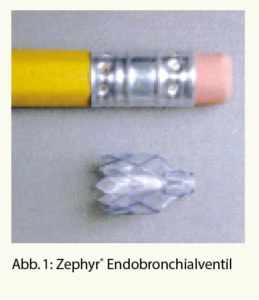

Das Ziel dieser Methode ist es, eine komplette Atelektase eines Lungenlappens zu erreichen und damit die Überblähung zu vermindern. Mittels Einlage von Einweg-Ventilen (Abb. 1) in den Segment- und Subsegmentbronchien in dem am meisten vom Emphysem betroffenen Lungenlappen wird ein unidirektionaler Luftfluss erzwungen. Das heisst, die Luft kann wohl während der Exspiration aus dem Lappen strömen, wird aber durch die Ventile bei der Inspiration blockiert, so dass es zu einer kontinuierlichen Entleerung des behandelten Lungenlappens kommt, im besten Fall zu einer Totalatelektase (Abb. 2).

Die häufigste Komplikation ist eine akute Exazerbation der COPD, welche in den ersten 90 Tagen nach Ventileinlage zu ca. 10% auftritt. Meistens ist dann eine kurzfristige Therapie mit systemischen Steroiden und einem Antibiotikum notwendig. Die häufigste periinterventionelle Komplikation (ca. 20% der Fälle) ist der Pneumothorax, welcher typischerweise in 90% der Fälle in den ersten 5 Tagen auftritt und meistens eine Thoraxdrainage nötig macht. Die Ursache liegt in der raschen Ausbildung der Atelektase, was zu Zugkräften am peripheren Lungengewebe führt. Tatsächlich profitieren aber gerade diese Patienten am meisten. Wegen des Pneumothorax-Risikos empfiehlt sich eine Hospitalisationszeit von 5 bis 7 Tagen. Durchschnittlich werden 5 Ventile benötigt. Die Einlage erfolgt mittels eines Kathetersystems über ein flexibles Bronchoskop entweder in Narkose oder aber auch nur unter Sedation beim spontan atmenden Patienten.